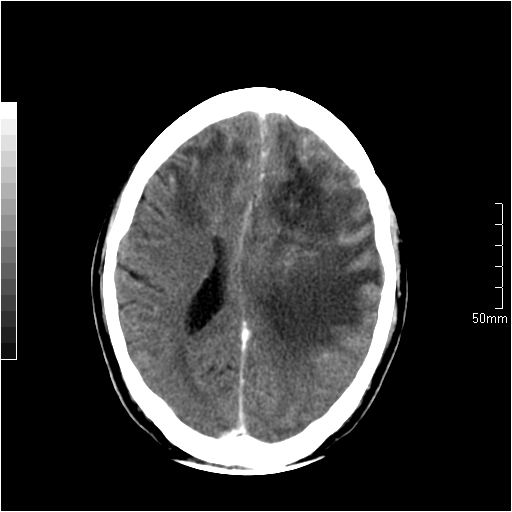

以下是引用天南地北在2007-6-25 12:39:00的发言:[br]有占位效应[br]支持术后复发

以下是引用zjzjr在2007-6-25 12:38:00的发言:[br]左侧复发,右侧转移。